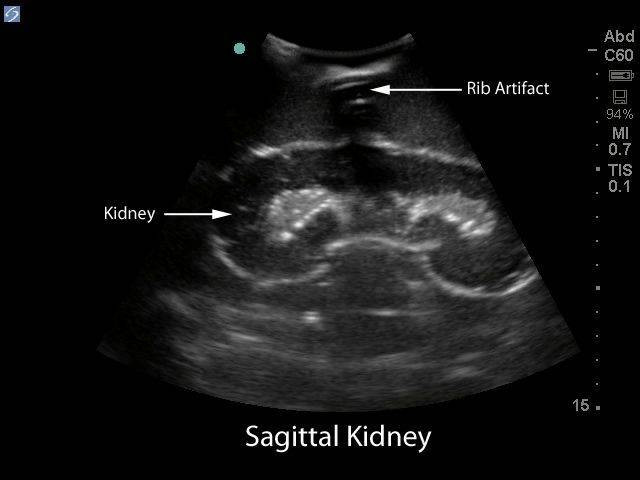

Renal Ultrasound Complete Protocol Sonographic Tendencies Kidney Biopsy Ultrasound The guidance method of choice is ultrasound. Ultrasound allows the doctor to. A kidney biopsy (sometimes called a renal biopsy) involves a very small sample of kidney tissue being removed. The radiologist will use the ultrasound scanner to guide a needle through the skin and. What is an ultrasound guided biopsy of the kidney? This core curriculum briefly outlines the. Kidney Biopsy Ultrasound.